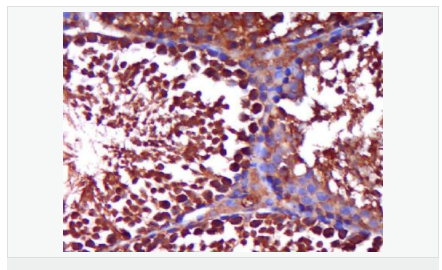

| 產(chǎn)品應用 | WB=1:500-2000 ELISA=1:5000-10000 IHC-P=1:100-500 IHC-F=1:100-500 Flow-Cyt=1ug/Test IF=1:100-500 (石蠟切片需做抗原修復) not yet tested in other applications. optimal dilutions/concentrations should be determined by the end user. |

| 產(chǎn)品介紹 | The androgen receptor gene is more than 90 kb long and codes for a protein that has 3 major functional domains: the N-terminal domain, DNA-binding domain, and androgen-binding domain. The protein functions as a steroid-hormone activated transcription factor. Upon binding the hormone ligand, the receptor dissociates from accessory proteins, translocates into the nucleus, dimerizes, and then stimulates transcription of androgen responsive genes. This gene contains 2 polymorphic trinucleotide repeat segments that encode polyglutamine and polyglycine tracts in the N-terminal transactivation domain of its protein. Expansion of the polyglutamine tract causes spinal bulbar muscular atrophy (Kennedy disease). Mutations in this gene are also associated with complete androgen insensitivity (CAIS). Two alternatively spliced variants encoding distinct isoforms have been described. [provided by RefSeq, Jul 2008] Function: Steroid hormone receptors are ligand-activated transcription factors that regulate eukaryotic gene expression and affect cellular proliferation and differentiation in target tissues. Transcription factor activity is modulated by bound coactivator and corepressor proteins. Transcription activation is down-regulated by NR0B2. Activated, but not phosphorylated, by HIPK3 and ZIPK/DAPK3. [ENZYME REGULATION] AIM-100 (4-amino-5,6-biaryl-furo[2,3-d]pyrimidine) suppresses TNK2-mediated phosphorylation at Tyr-267. Inhibits the binding of the Tyr-267 phosphorylated form to androgen-responsive enhancers (AREs) and its transcriptional activity. Subunit: Binds DNA as a homodimer. Part of a ternary complex containing AR, EFCAB6/DJBP and PARK7. Interacts with HIPK3 and NR0B2 in the presence of androgen. The ligand binding domain interacts with KAT7/HBO1 in the presence of dihydrotestosterone. Interacts with EFCAB6/DJBP, PELP1, PQBP1, RANBP9, RBAK, SPDEF, SRA1, TGFB1I1, ZNF318 and RREB1. Interacts with ZMIZ1/ZIMP10 and ZMIZ2/ZMIP7 which both enhance its transactivation activity. Interacts with SLC30A9 and RAD54L2/ARIP4. Interacts via the ligand-binding domain with LXXLL and FXXLF motifs from NCOA1, NCOA2, NCOA3, NCOA4 and MAGEA11. The AR N-terminal poly-Gln region binds Ran resulting in enhancement of AR-mediated transactivation. Ran-binding decreases as the poly-Gln length increases. Interacts with HIP1 (via coiled coil domain). Interacts (via ligand-binding domain) with TRIM68. Interacts with TNK2. Interacts with USP26. Interacts with RNF6. Interacts (regulated by RNF6 probably through polyubiquitination) with RNF14; regulates AR transcriptional activity. Interacts with PRMT2 and TRIM24. Interacts with GNB2L1/RACK1. Interacts with RANBP10; this interaction enhances dihydrotestosterone-induced AR transcriptional activity. Interacts with PRPF6 in a hormone-independent way; this interaction enhances dihydrotestosterone-induced AR transcriptional activity. Interacts with STK4/MST1. Interacts with ZIPK/DAPK3. Interacts with LPXN. Interacts with MAK. Part of a complex containing AR, MAK and NCOA3. Subcellular Location: Nucleus. Cytoplasm. Note=Predominantly cytoplasmic in unligated form but translocates to the nucleus upon ligand-binding. Can also translocate to the nucleus in unligated form in the presence of GNB2L1. Tissue Specificity: Isoform 2 is mainly expressed in heart and skeletal muscle. Post-translational modifications: Sumoylated on Lys-386 (major) and Lys-520. Ubiquitinated. Deubiquitinated by USP26. 'Lys-6' and 'Lys-27'-linked polyubiquitination by RNF6 modulates AR transcriptional activity and specificity. Phosphorylated in prostate cancer cells in response to several growth factors including EGF. Phosphorylation is induced by c-Src kinase (CSK). Tyr-534 is one of the major phosphorylation sites and an increase in phosphorylation and Src kinase activity is associated with prostate cancer progression. Phosphorylation by TNK2 enhances the DNA-binding and transcriptional activity and may be responsible for androgen-independent progression of prostate cancer. Phosphorylation at Ser-81 by CDK9 regulates AR promoter selectivity and cell growth. Phosphorylation by PAK6 leads to AR-mediated transcription inhibition. Palmitoylated by ZDHHC7 and ZDHHC21. Palmitoylation is required for plasma membrane targeting and for rapid intracellular signaling via ERK and AKT kinases and cAMP generation. DISEASE: Defects in AR are the cause of androgen insensitivity syndrome (AIS) [MIM:300068]; previously known as testicular feminization syndrome (TFM). AIS is an X-linked recessive form of pseudohermaphroditism due end-organ resistance to androgen. Affected males have female external genitalia, female breast development, blind vagina, absent uterus and female adnexa, and abdominal or inguinal testes, despite a normal 46,XY karyotype. Defects in AR are the cause of spinal and bulbar muscular atrophy X-linked type 1 (SMAX1) [MIM:313200]; also known as Kennedy disease. SMAX1 is an X-linked recessive form of spinal muscular atrophy. Spinal muscular atrophy refers to a group of neuromuscular disorders characterized by degeneration of the anterior horn cells of the spinal cord, leading to symmetrical muscle weakness and atrophy. SMAX1 occurs only in men. Age at onset is usually in the third to fifth decade of life, but earlier involvement has been reported. It is characterized by slowly progressive limb and bulbar muscle weakness with fasciculations, muscle atrophy, and gynecomastia. The disorder is clinically similar to classic forms of autosomal spinal muscular atrophy. Note=Caused by trinucleotide CAG repeat expansion. In SMAX1 patients the number of Gln ranges from 38 to 62. Longer expansions result in earlier onset and more severe clinical manifestations of the disease. Note=Defects in AR may play a role in metastatic prostate cancer. The mutated receptor stimulates prostate growth and metastases development despite of androgen ablation. This treatment can reduce primary and metastatic lesions probably by inducing apoptosis of tumor cells when they express the wild-type receptor. Defects in AR are the cause of androgen insensitivity syndrome partial (PAIS) [MIM:312300]; also known as Reifenstein syndrome. PAIS is characterized by hypospadias, hypogonadism, gynecomastia, genital ambiguity, normal XY karyotype, and a pedigree pattern consistent with X-linked recessive inheritance. Some patients present azoospermia or severe oligospermia without other clinical manifestations. Similarity: Belongs to the nuclear hormone receptor family. NR3 subfamily. Contains 1 nuclear receptor DNA-binding domain. SWISS: P10275 Gene ID: 367 Database links: Entrez Gene: 367 Human Entrez Gene: 11835 Mouse Omim: 313700 Human SwissProt: P10275 Human SwissProt: P19091 Mouse Unigene: 496240 Human Unigene: 39005 Mouse Unigene: 394224 Mouse Unigene: 439657 Mouse Unigene: 9813 Rat Important Note: This product as supplied is intended for research use only, not for use in human, therapeutic or diagnostic applications. AR是一個由917個氨基酸組成的蛋白質(zhì),位于雄激素靶組織細胞中或細胞表面上的特異分子部位或結(jié)構(gòu)。 AR在前列腺癌中起著重要的作用,研究表明AR的表達與組織分型形成一定的相關(guān)性 ,AR在高分化的腫瘤中表達較多,而在低分化的腫瘤中表達較少。用于前列腺癌的檢測,指導臨床治療,目前可用于乳腺癌、食道癌等各項腫瘤的研究。 |